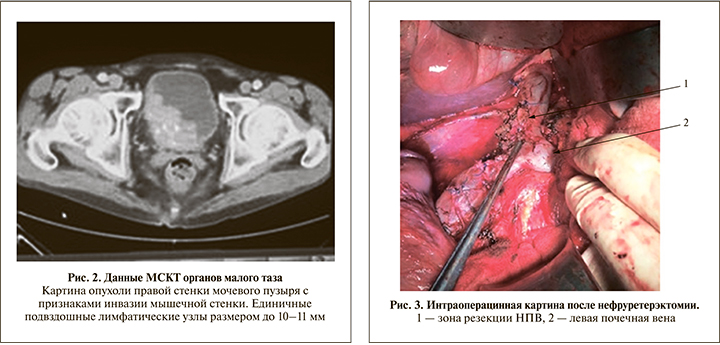

Пациент Б. 61 года в апреле 2016 г. госпитализирован в экстренном порядке в урологическое отделение ГКБ им. С. П. Боткина с жалобами на тотальную безболевую макрогематурию со сгустками, общую слабость. Из анамнеза известно, что эпизоды макрогематурии отмечал в течение 1,5 лет, не обследовался. По результатам проведенного обследования (УЗИ, МСКТ, рентгенография органов грудной клетки, остеосцинтиграфия) установлен диагноз «опухоль правой почки сТ3aN0M0, опухоль мочевого пузыря сТ3bN0M0» (рис. 1, 2).

25.04.2016 проведены следующие операции: радикальная нефруретерэктомия справа, тромбэктомия с резекцией нижней полой вены, расширенная забрюшинная лимфаденэктомия, радикальная цистпростатвезикулэктомия, расширенная тазовая лимфадэнктомия, уретерокутанеостомия слева (хирург – академик О. Б. Лоран). Интраоперационно в правой половине брюшной полости определена опухоль больших размеров (около 20 см), исходившая из правой почки. Нижняя полая вена (НПВ) сдавлена опухолью. Просвет значительно расширенной правой почечной вены (ППВ) полностью замещен каменистой плотности опухолевым тромбом с выходом в просвет НПВ на протяжении 2 см. Нижняя полая вена выше и ниже тромба, а также левая почечная вена блокированы турникетами, правая почечная артерия мобилизована в аортокавальном промежутке, на нее наложен сосудистый зажим. На стенку полой вены наложен зажим Сатинского и проведена каватомия с полным иссечением устья ППВ – тромб удален полностью. Дефект НПВ длиной 8 см ушит двухрядным проленовым швом 5/0 (рис. 3).